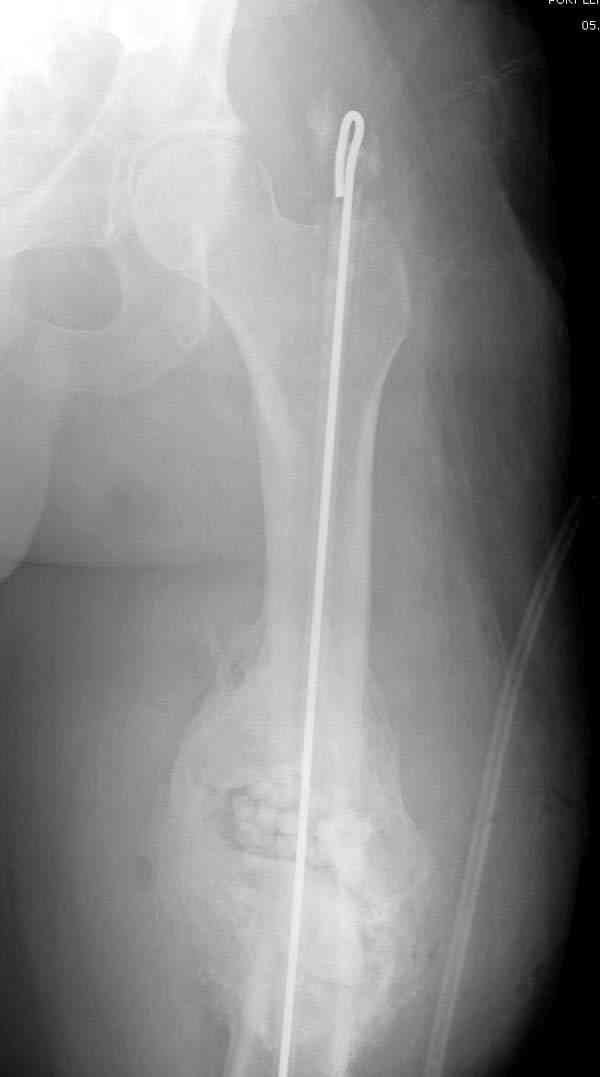

После нескольких некрэктомий, проведения аутодермопластики и заживдения ожоговой раны через 2 месяца после травмы произведен открытый остеосинтез левой бедренной кости штифтом и пластиной (деротационной) [image 01, 02]. Через 1 год и 7 месяцев после травмы у больного диагностированы ложный сустав и хронический остеомиелит левой бедренной кости. Произведено удаление металлических фиксаторов, секвестрэктомия и остеосинтез бедренной костивнешним двухплоскостным стержневым аппаратом [image 03, 04] .

Через 3 года после травмы констатировало отсутствие консолидации бедренной кости, сохранение признаков хронического остеомиелита (свищ в нижней трети левого бедра). Произведен демонтаж аппарата, реостеосинтез бедренной кости спице-стержневым аппаратом, некрсеквестрэктомия. В аппарате удалось лишь частично произвестиустранение углообразной деформации бедренной кости [image 05] .